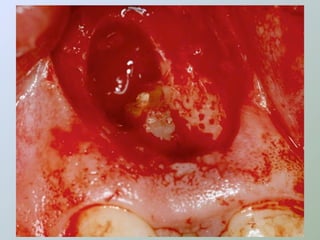

CURETAGEM

O tecido inflamatório em torno do

ápice radicular deve ser removido

para:

• Ganhar acesso e melhorar a

visibilidade

• Obter material para histopatológico

• Reduzir a hemorragia

• Evitar danos aos dentes

adjacentes

• Procurar remover a totalidade da

lesão

• Porção retro-radicular

• Uso de agentes hemostáticos

Ressecção do

ápice radicular

- apicectomia -

apicectomia

• Acesso ao canal para

exame e inserção de

material obturador

• Para remover uma porção

não debridada/obturada

da raiz